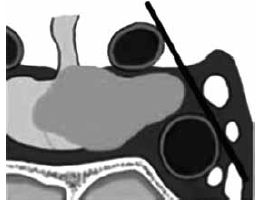

Um macroadenoma que possui extensão lateral que termina entre a linha intercarotídea e a margem lateral do seio cavernoso é classificado como KNOSP: